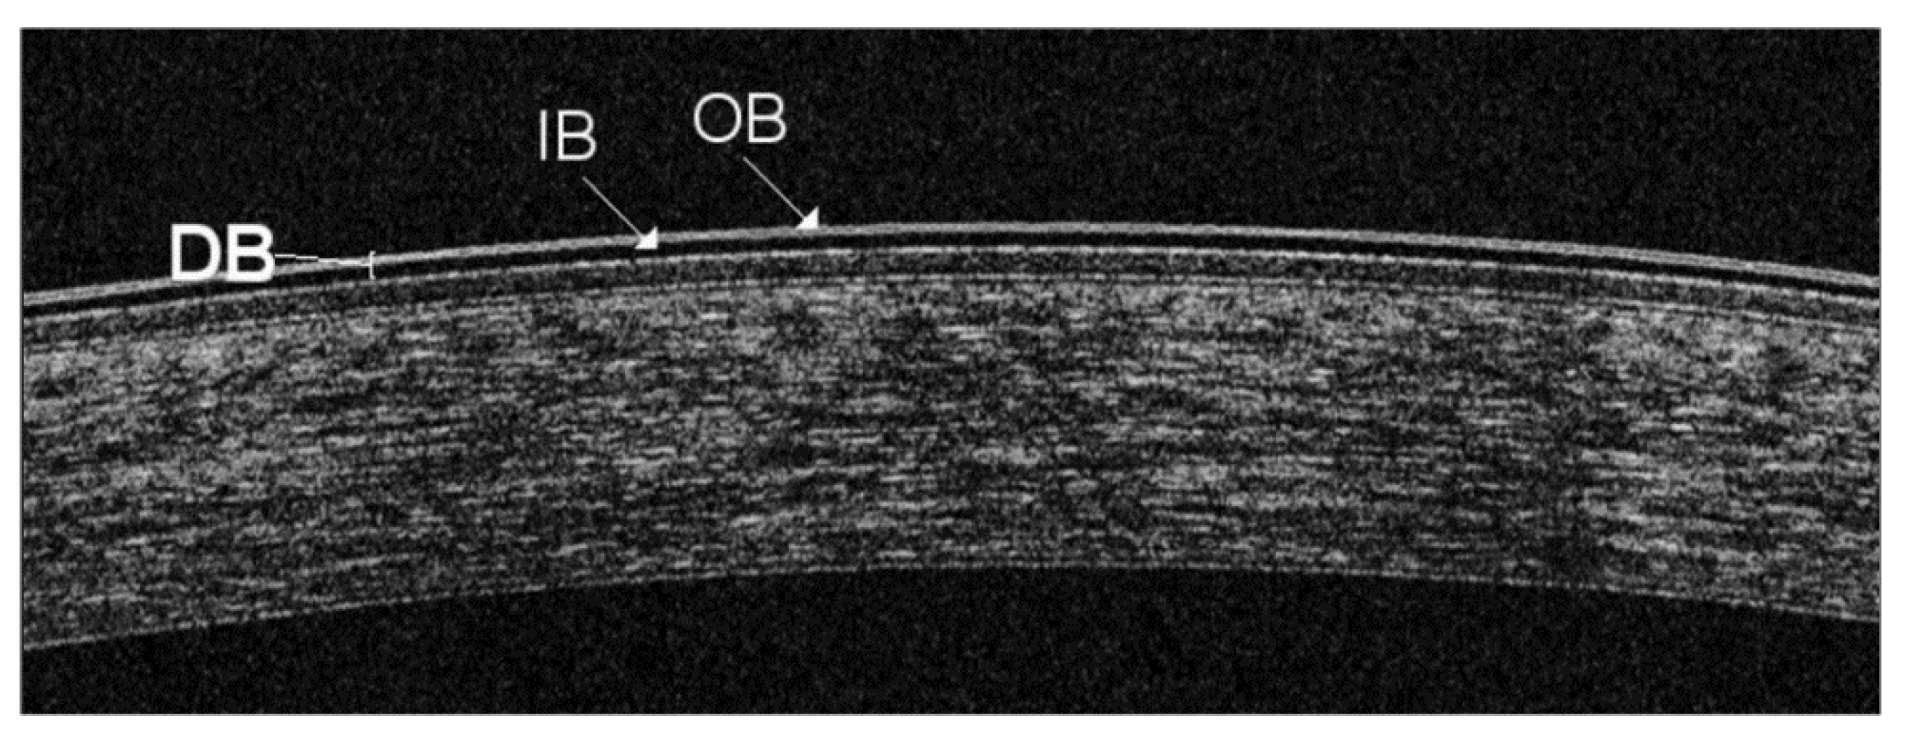

- Bai, Y.; Nichols, J.J. Advances in thickness measurements and dynamic visualization of the tear film using non-invasive optical approaches. Prog. Retin. Eye Res. 2017, 58, 28–44. [Google Scholar] [CrossRef]

- Wang, J.; Fonn, D.; Simpson, T.L.; Jones, L. Precorneal and pre- and postlens tear film thickness measured indirectly with optical coherence tomography. Invest Ophthalmol. Vis. Sci. 2003, 44, 2524–2528. [Google Scholar] [CrossRef]

- Yadav, R.; Lee, K.S.; Rolland, J.P.; Zavislan, J.M.; Aquavella, J.V.; Yoon, G. Micrometer axial resolution OCT for corneal imaging. Biomed Optic. Express 2011, 2, 3037–3046. [Google Scholar] [CrossRef]

- Werkmeister, R.M.; Alex, A.; Kaya, S.; Unterhuber, A.; Hofer, B.; Riedl, J.; Bronhagl, M.; Vietauer, M.; Schmidl, D.; Schmoll, T.; et al. Measurement of tear film thickness using ultrahigh-resolution optical coherence tomography ultrahigh-resolution OCT measurement of tear film. Investig. Ophthalmol. Vis. Sci. 2013, 54, 5578–5583. [Google Scholar] [CrossRef] [PubMed]